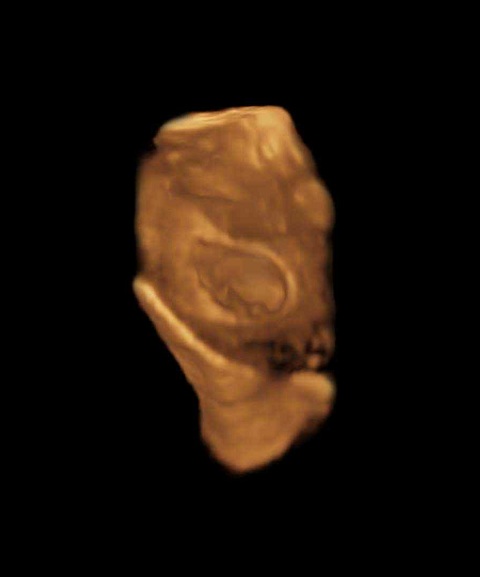

三维图

进入怀孕第6周后,在你的子宫里,胚胎正在迅速地成长,他(她)的心脏已经开始划分心室,并进行有规律的跳动及开始供血。这周的细胞还在迅速地分裂,主要器官包括初级的肾和心脏的雏形都已发育,神经管开始连接大脑和脊髓,原肠也开始发育。

胚胎的上面和下面开始长出肢体的幼芽,这是将来孩子的手臂和腿。日后将形成嘴巴的地方的下部,有一些小皱痕,它最终会发育成脖子和下颌。在本周面部的基本器官已经开始成形,已经能清晰地看到鼻孔,眼睛的雏形也已经具备。